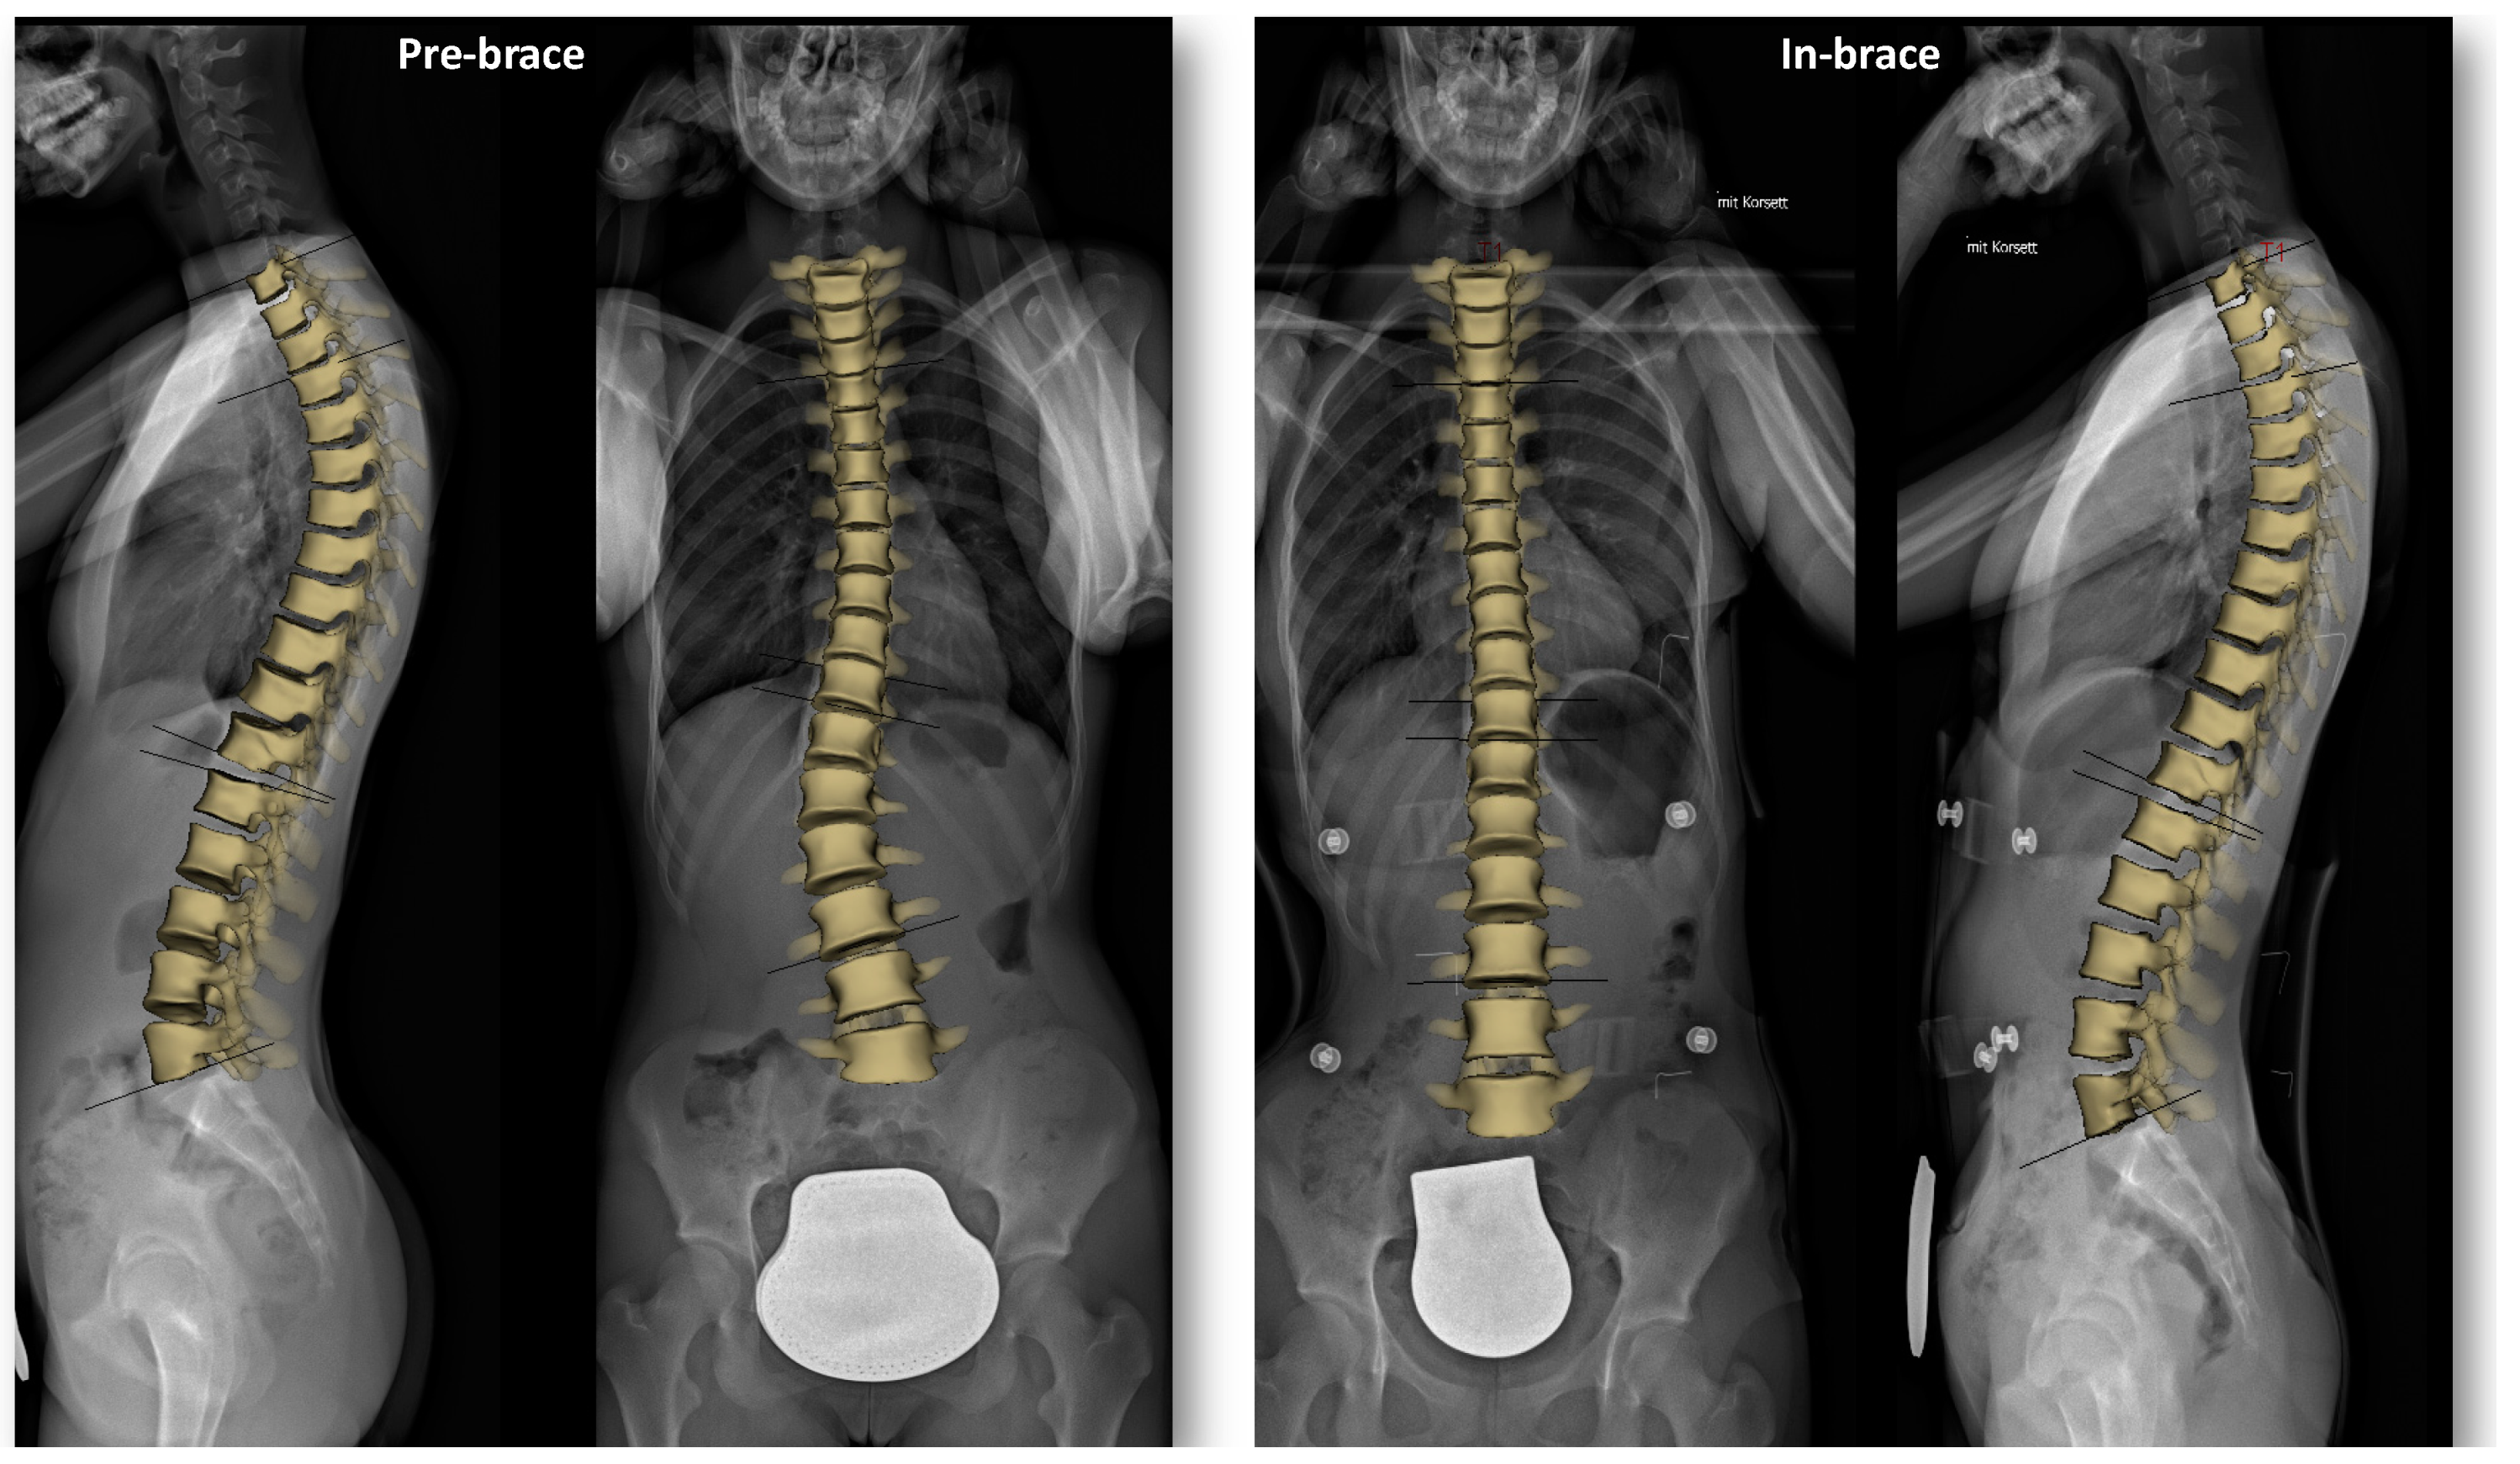

Three-Dimensional Analysis of Initial Brace Correction in the Setting of Adolescent Idiopathic Scoliosis

2.2. Radiographic Acquisition and Tridimensional Reconstruction